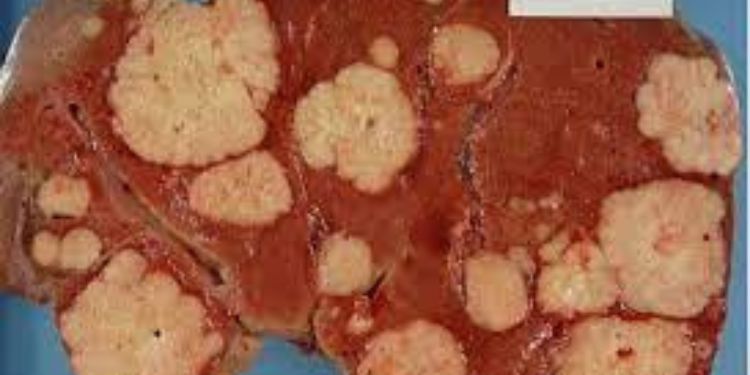

Future of Cancer Care: Research in Skin, Breast, and Prostate Cancers

Journal of Neoplasms encourages the exploration of diverse research topics within the field of neoplasms, promoting interdisciplinary studies and the advancement of knowledge in related areas of Skin Cancer Breast Cancer, Basal Cell Carcinoma, Pancreatic Cancer, Prostate Cancer, Cervical Cancer.

Comprehensive Guide for Leukemia, Skin Cancer, Breast Cancer Articles